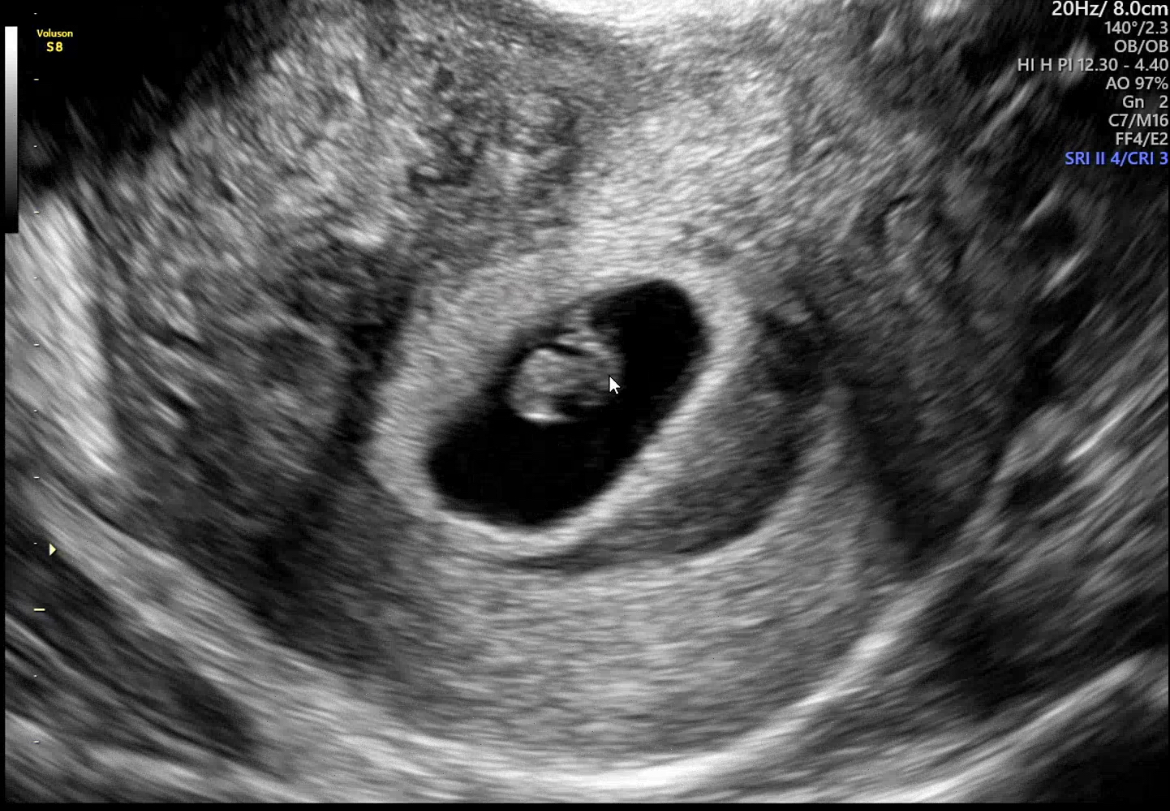

| 가슴 떨리는 임신 이야기를 공유해 주세요. | 인공수정 2차 모두 실패한 후, 긴장과 기대가 섞인 마음으로 시험관 시술을 시작했습니다. 매일 자가 주사를 맞으며 긴 시간을 견뎌냈고, 배아이식 후에는 스스로를 다독이며 하루하루 떨리는 마음으로 기다린 끝에 아기천사가 찾아와 주었습니다. |

| 치료 도중 느꼈던 가장 기뻤던 순간과 절망적인 것들은 무엇인가요? 잊지 못할 경험이 있나요? | 확률이 낮다고는 했지만 인공수정 2회 모두 실패했을 때가 가장 절망적이었습니다. 반대로 가장 기뻤던 순간은 배아이식 후 첫 피검사 결과를 들었던 날로, 그 순간의 기쁨은 지금도 잊을 수 없습니다. |